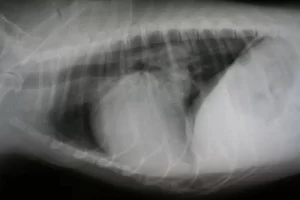

When your pets are not feeling well, we might recommend radiographs. They allow us to see what is going on inside your pets without surgery. We are able to get amazing pictures using digital radiology.